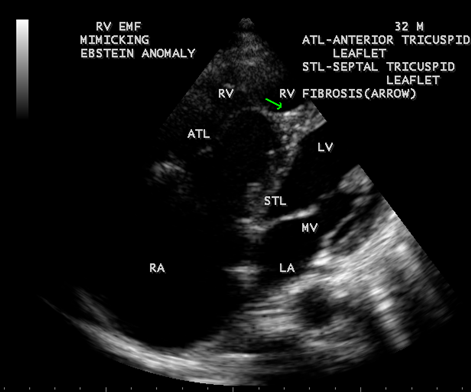

Figure 38: Right ventricular Endomyocardial fibrosis mimicking as Ebstein anomaly in a 32- year old male.

When the endocardium is replaced by collagenous fibrosis (consist of collagen deposition and fibroblast proliferation), the final fibrotic stage is reached after several years of disease activity. Fibrotic obliteration of the apices of the affected ventricles is the hallmark of the disorder and fibrosis involving the papillary muscles and chordae tendineae leading to atrioventricular valve distortion and regurgitation. In the left ventricle, the fibrosis extends from the apex to the posterior mitral leaflet, usually sparing the anterior mitral leaflet and outflow tract and cause PML (posterior mitral leaflet) distortion and regurgitation. Like the peculiar geographical distribution, the fibrotic endomyocardial involvement stops short of the ventricular outflow tract like a ridge [17] as shown in Figures 15,29,31,35 and 44. The fibrotic tissue often creates a nidus for thrombus formation, which can be extensive. Atrial thrombi also occur and the right atrium may be aneurysmally dilated. Aneurysmal right atrium with spontaneous echo contrast was detected in a 32- year old male as shown in Figure 36 [18- Figure 3]. In addition, there are fibrosis and granular septation extending into the underlying myocardial tissue and myocyte hypertrophy is common [19]. Fibrotic process causes tethering of leaflets into ventricular walls and may mimic Ebstein’s malformation as shown in Figure 38[20],[21]. Fibrosis increases the stiffness of the heart, resulting restrictive physiology, AV (atrioventricular) valve regurgitation which has been linked to atrial arrhythmias such as atrial fibrillation as shown in Figures 19 and 20 in a 62-year old female. Atrial fibrillation has been reported in more than 30% of patients with EMF. Fibrosis impairs activation patterns of the conduction system and may provide substrate for wave breaks and reentry [22]. Fibrosis reduces conduction velocity and cause conduction abnormalities like junctional rhythms, heart blocks as shown in Figure 21 and 22 in a 75-year old female and atrioventricular conduction delay [23].